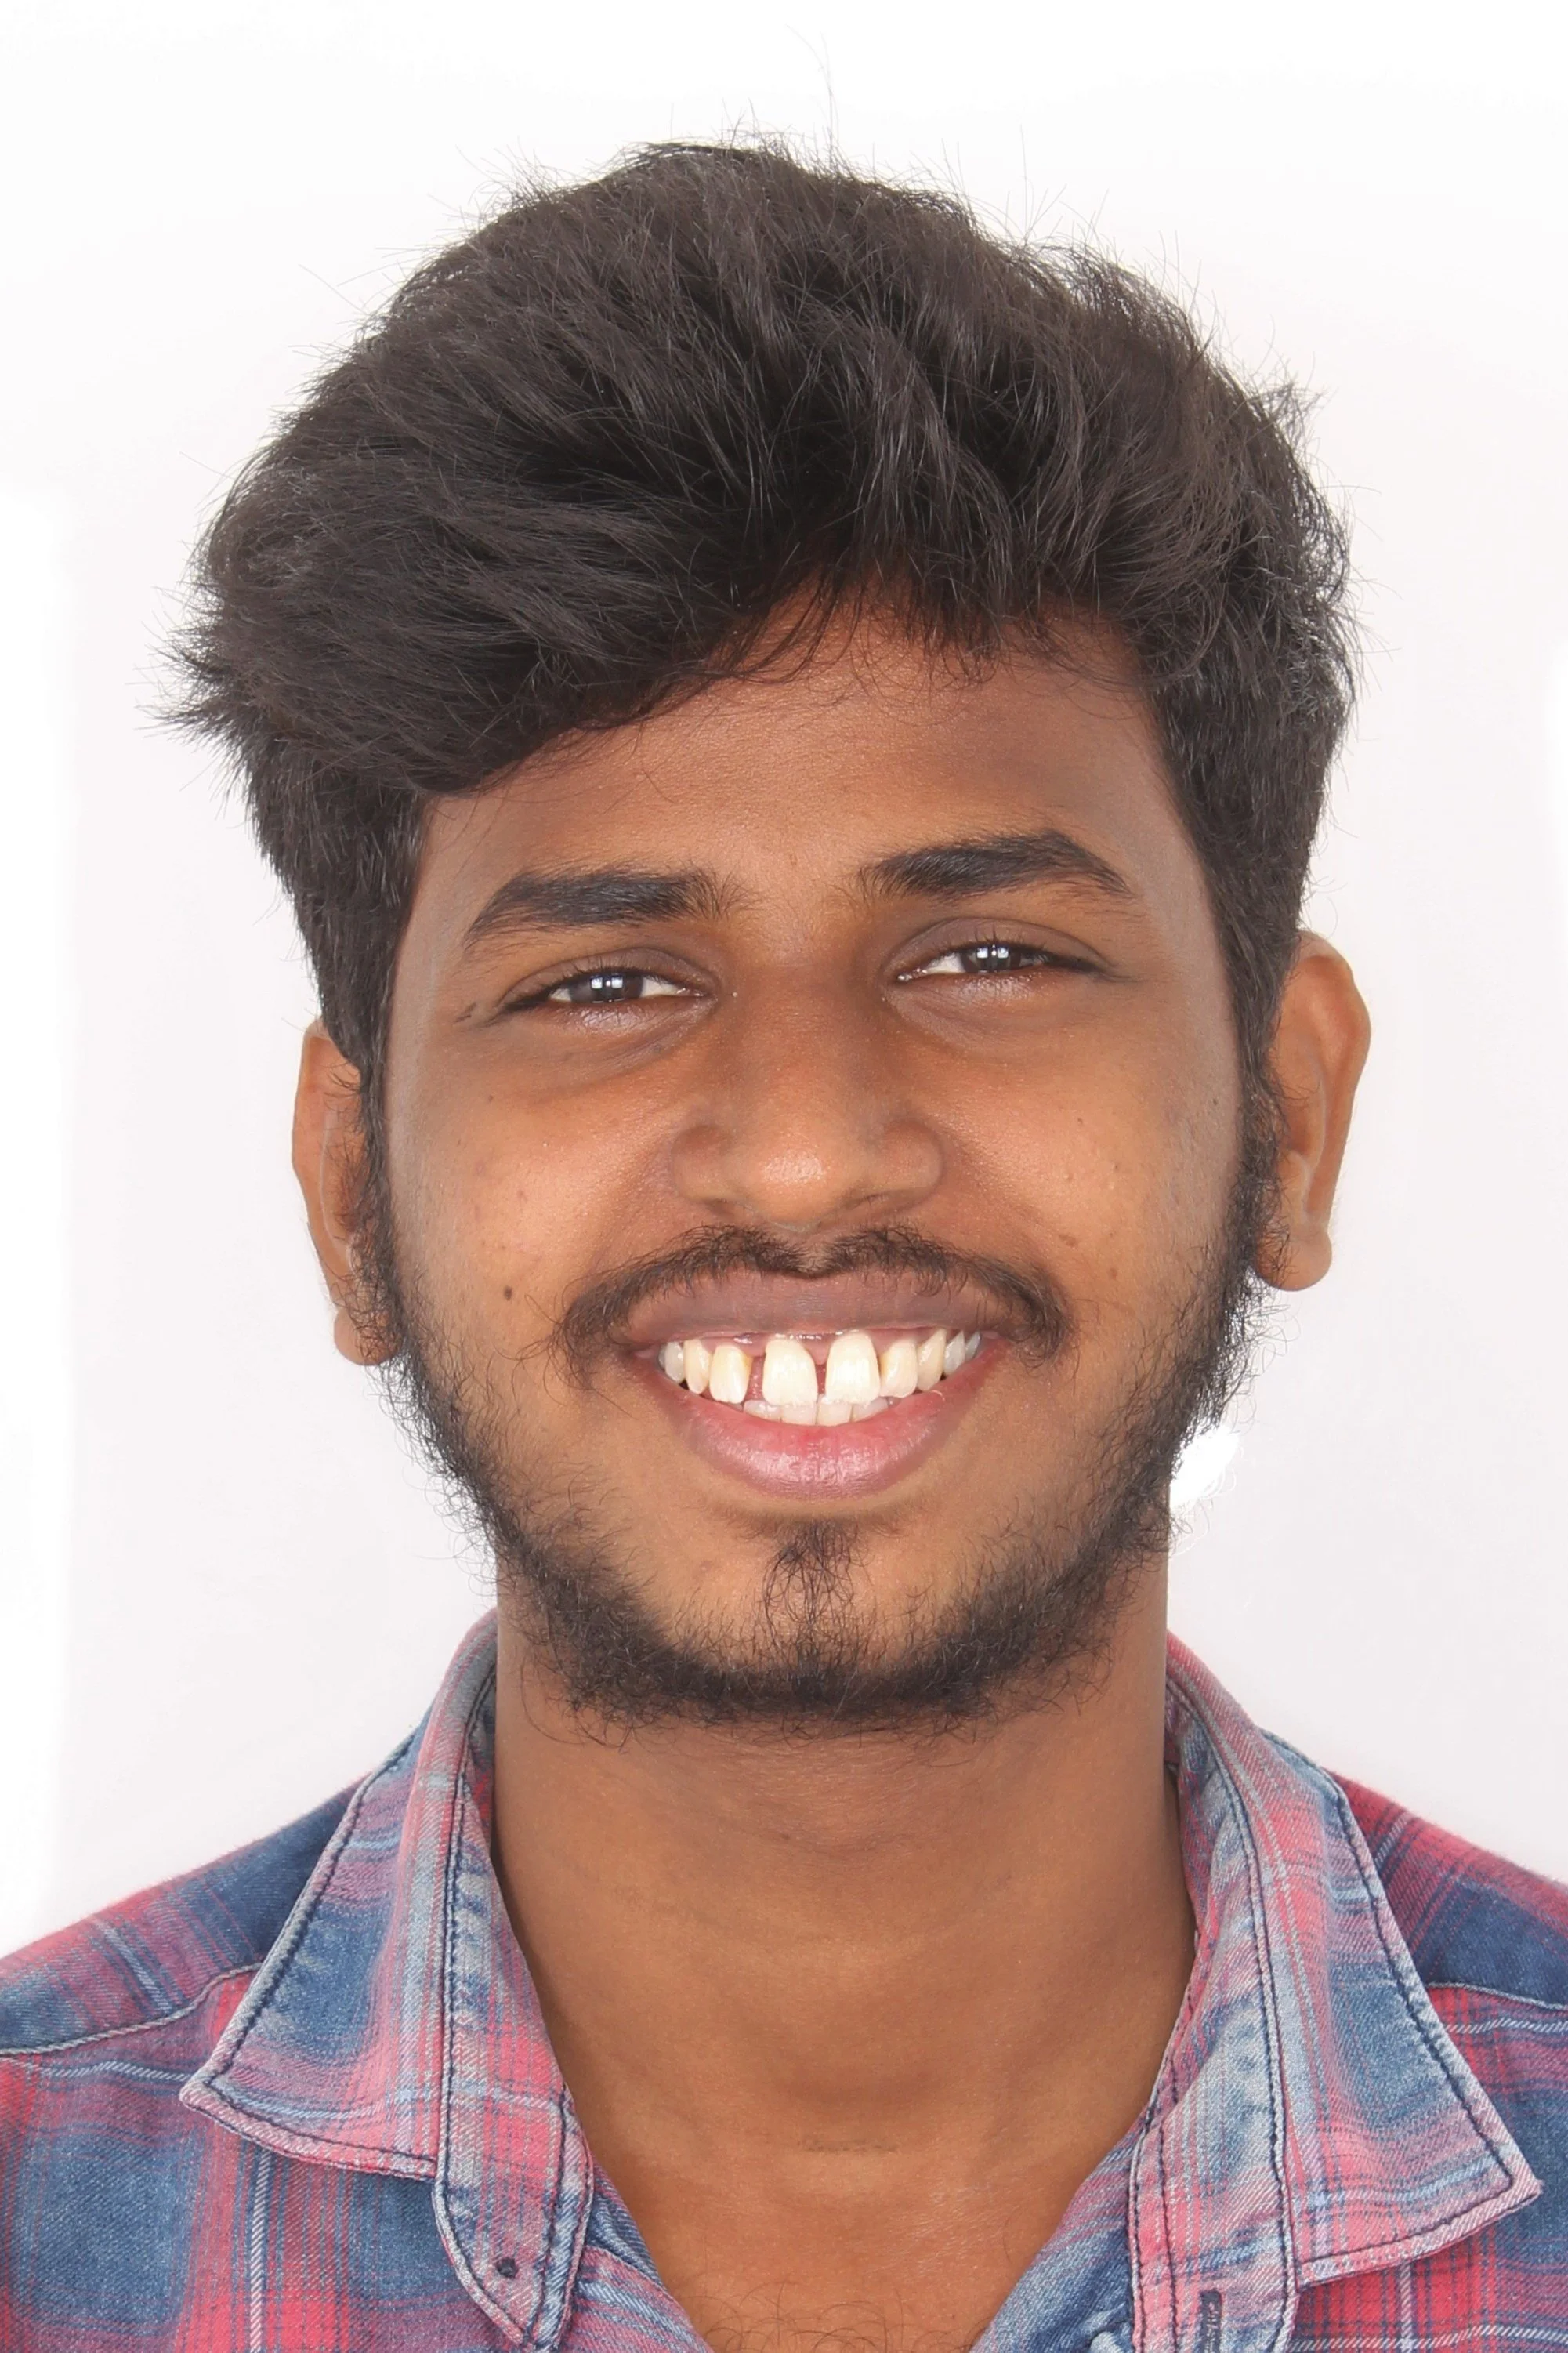

ARCH ALIGNMENT - DECROWDING THE MALPOSED TEETH

ARCH ALIGNMENT - DECROWDING THE MALPOSED TEETH

DECROWDING THE MALPOSED DENTITION

DECROWDING THE MALPOSED DENTITION